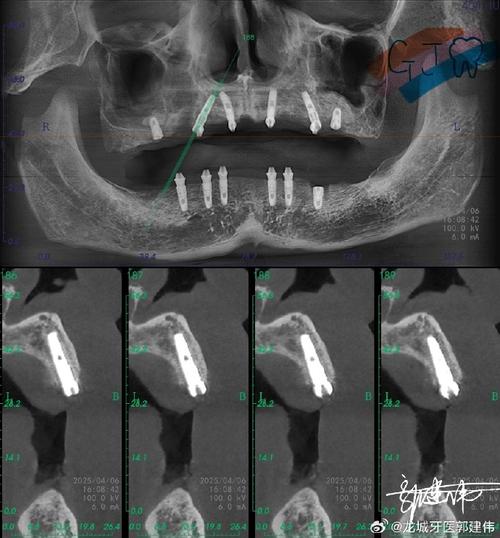

- 术前评估:通过CBCT(锥形束CT)测量骨缺损的体积、密度及与重要解剖结构(如下牙槽神经、上颌窦)的关系,制定个性化植骨方案。